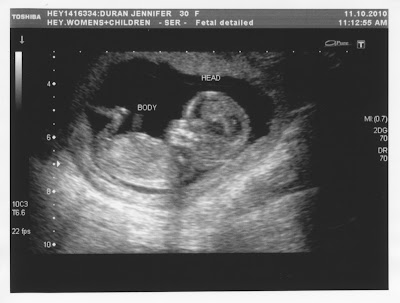

It was great to see more of the baby at our 20-week ultrasound and such a relief to hear that all is well.

We decided not to find out the gender until birth so the suspense is starting to build!!